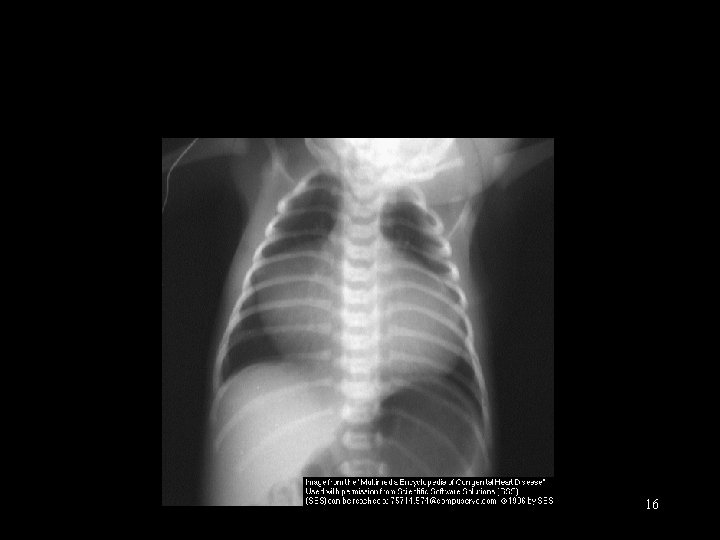

CXR § Heart size § Pulmonary blood flow § Cardiac position 15

16

Ebstein’s anomaly 17